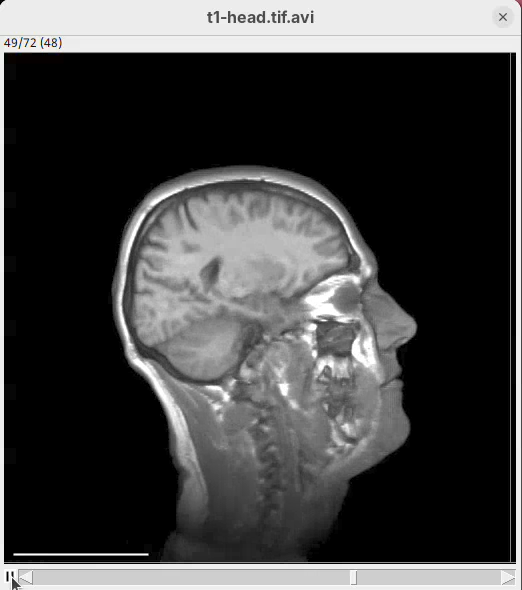

3D Project

This is a simple tool to quickly generate a 3D animation (e.g., 360-degree rotation) from an image stack. There are basic parameters for adjusting the rendering, like projection method and opacity, and for controlling the animation. There’s only a bit of documentation. To try:

- Go to

Image>Stacks>3D Project...and clickOKto generate a basic animation.

As noticeable above, 3D Project doesn’t do so well with our MRI dataset. However, it works OK for fluorescent microscopy images, so I encourage you to try with other datasets in the future.